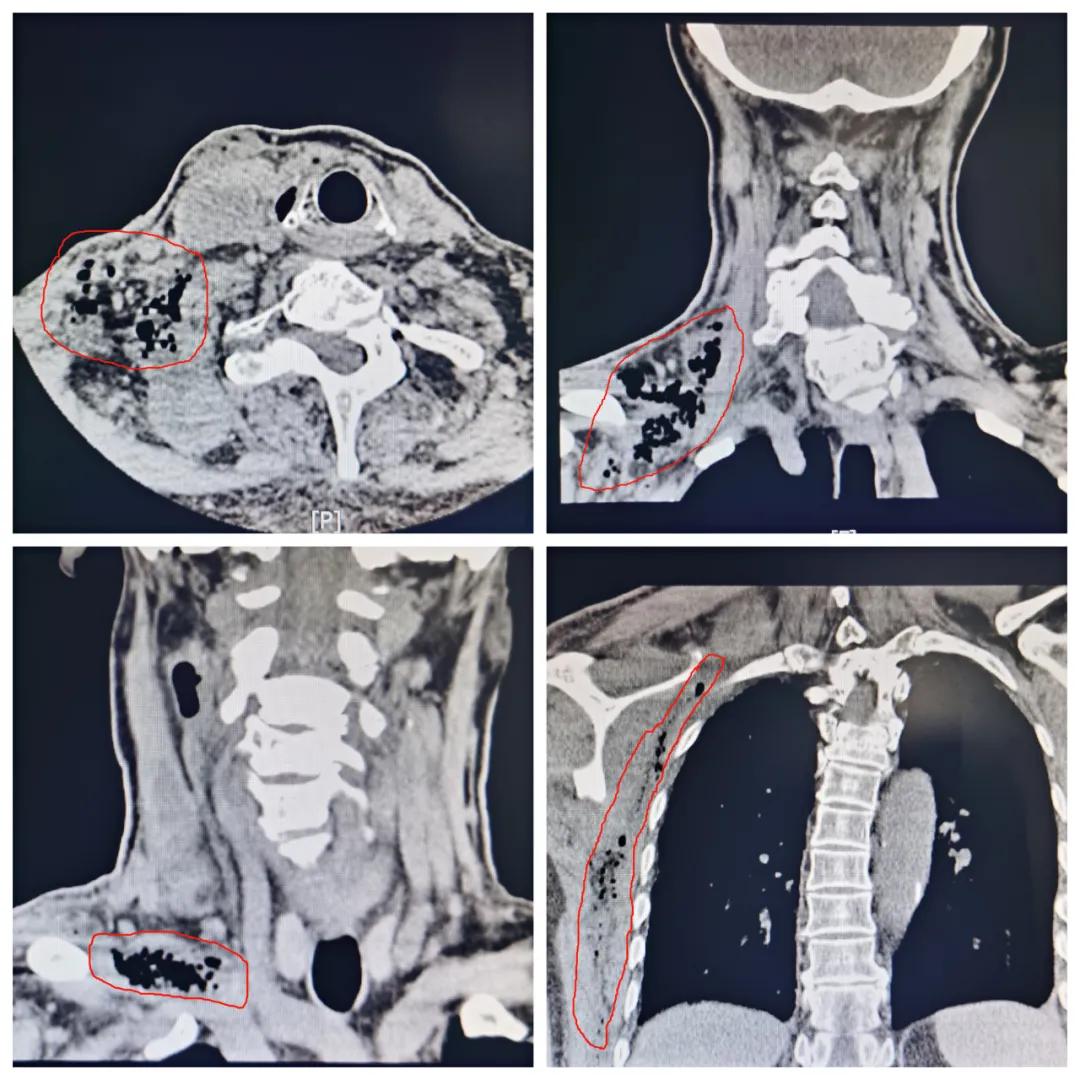

入院检查发现,老贾的 炎症已经蔓延扩散,感染范围很大:

从颅底、咽旁、颌下、颈部、锁骨下,到腋下及胸侧壁 ,这一大片区域皮肤红肿隆起,有压痛感,在喉镜下见到 会厌脓肿已经破裂溃烂 。

▲红色标注区域为感染区域